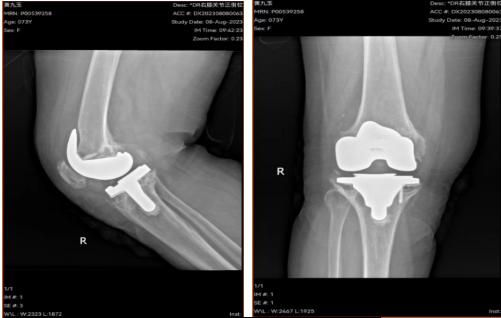

翻修术后DR

由于因黄某为初次膝关节置换术后感染患者,虽经清创后感染已经控制,其膝关节股骨侧及胫骨侧均存在骨缺损,给翻修手术带来了很大的困难。为此,杨正杰团队反复讨论治疗方案,详细制定手术计划,在与患者及家属详细沟通,充分告知手术风险后,得到了患者和家属的信任和支持。完善各项术前准备后,2024年1月24日,杨正杰主任医师主刀,杜润中、杨柳主治医师为助手的医疗团队,为患者实施了“膝关节翻修手术”,在麻醉科主任医师谯凌和手术室田霞护理团队的精心配合下,历时4小时,圆满地完成了手术。

术后,杨正杰为黄某制定了康复计划,科室护士长杨娟带着团队悉心护理,次日黄某便能辅助下床行走,激动地表示:“感谢铜仁市人民医院关节外科的医护人员,不仅技术精湛,而且护理精心,谢谢你们!”